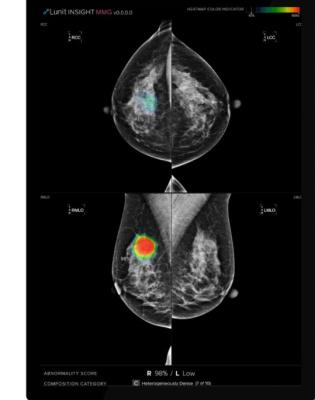

Developed using Lunit’s deep learning technology, Lunit Insight MMG accurately analyses mammography images to detect lesions that could indicate breast cancer and provides location information for any detected lesions in the form of outlines and heatmaps. The computer-assisted diagnostic software has shown excellent performance in the early detection of breast cancer.

With Lunit Insight MMG, rapid triage of screening mammograms will filter out benign cases for later evaluation, helping to reduce strain on radiologists as 60% of screening mammograms come up normal.